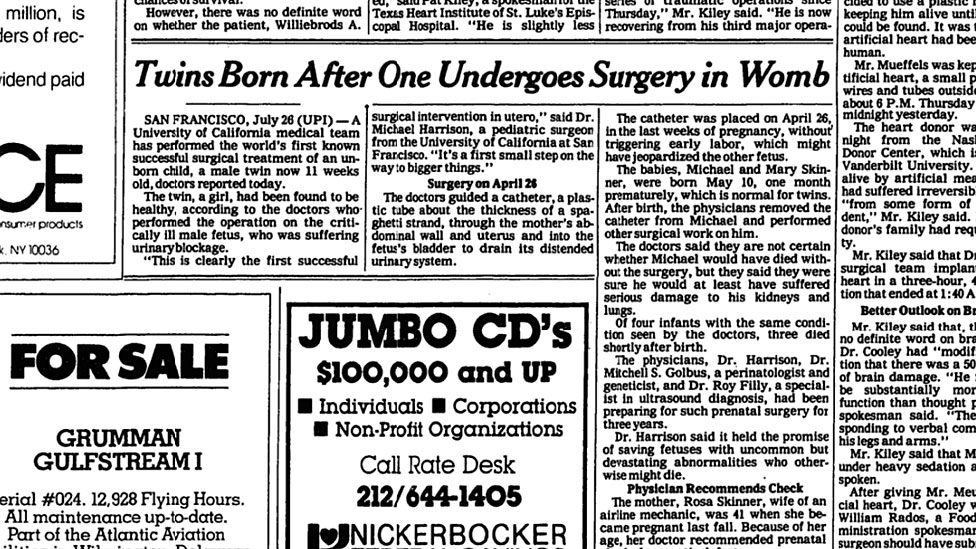

A pesar del enorme logro, el caso no fue revelado a la prensa. Recién se dio a conocer tres meses más tarde y de forma acallada.

"No queríamos que esto fuera un gran evento público, queríamos que nuestro trabajo fuera revisado por pares y publicado. Una de nuestras reglas era que todos los casos fueran revisados y publicados, tanto los buenos como los malos", reveló Harrison.